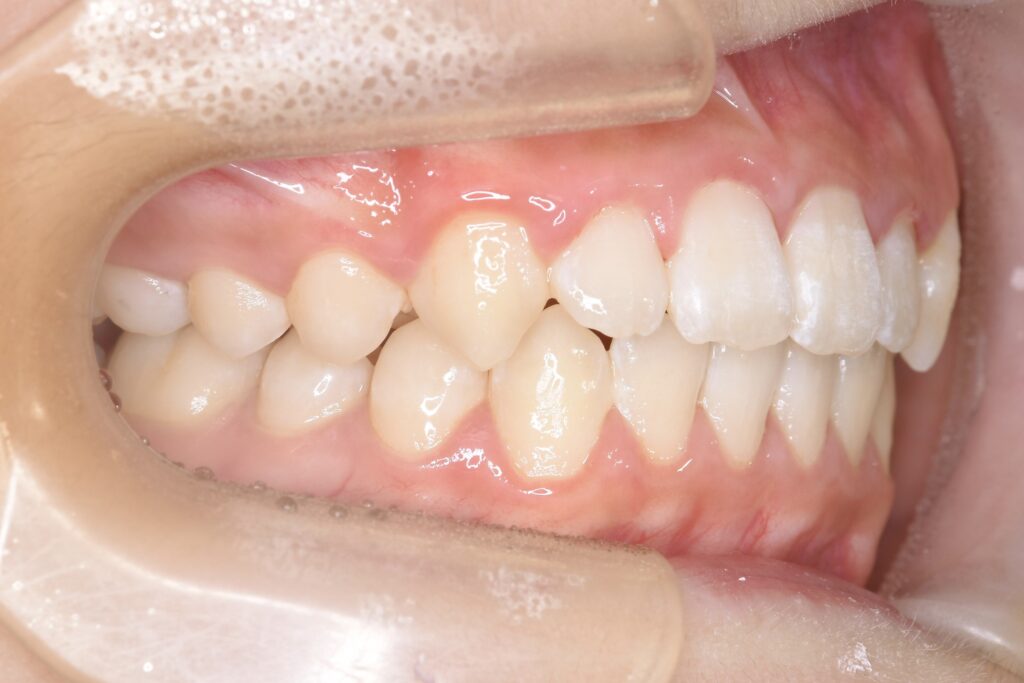

7歳 男児 小児矯正

BEFORE

主訴 通っている歯医者で矯正した方がいいと言われて気になっている。下の前歯がでこぼこしている。

診断名・主な症状 下顎前歯の叢生を伴う過蓋咬合

治療内容 上下の歯並びの幅を拡げつつ、前歯の関係を改善しました。

使用装置 急速拡大装置

リンガルアーチ

機能的矯正装置(マイオブレース)

抜歯部位 抜歯なし

治療期間 2年 + 後戻り止め期間(3年 )

通院回数 20回

費用 50万円程度(税別)  29331

リスク・副作用 痛み、歯肉退縮、歯根吸収、抜歯に伴う出血や腫れが生じることがあります。